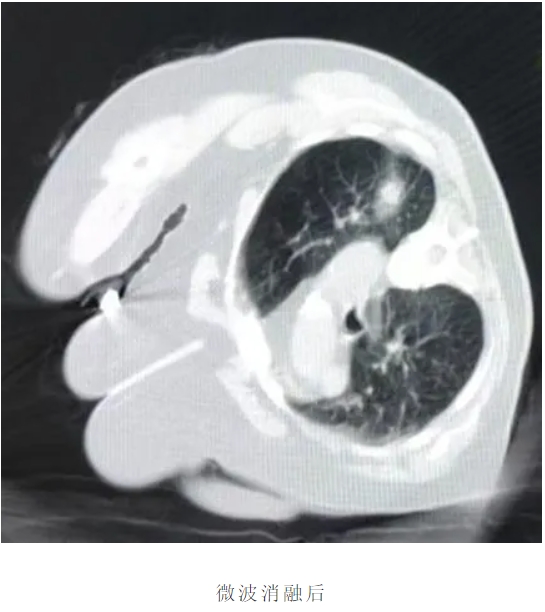

近日兴安盟人民医院胸外科团队成功完成院内首例肺结节微波消融术。在多模态影像导航系统引导下,直径仅1.8毫米的消融针如"精准导弹"直抵肺结节病灶,通过高频微波震荡产生局部高温,在数分钟内完成直径2.3厘米结节的完全灭活。同期开展的肺占位减瘤消融术,为晚期肺癌患者实现肿瘤负荷精准控制;联合实施的活检消融一体化技术,更在获取病理标本的同时完成肿瘤边缘灭活,开创"诊断+治疗"一站式微创诊疗先河。

首例接受治疗的79岁患者杨女士感慨:"原以为要开胸切肺,没想到躺一会就做完了手术,背部只有个创可贴。"术后CT显示,其右肺上叶结节完全消融,肺组织无渗血、无气胸。我科为患者提供从影像筛查、消融治疗到术后康复的全周期管理,实现"入院24小时内完成诊疗、48小时内出院"的日间手术模式。